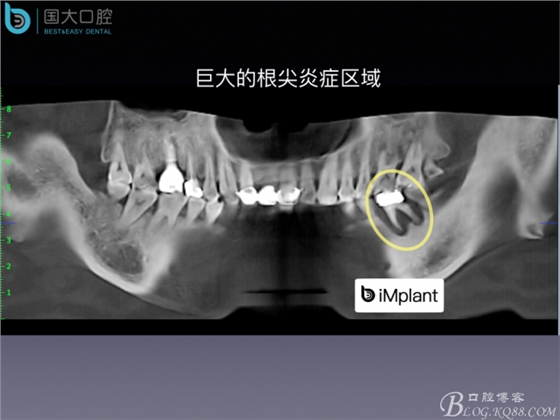

20160715154347_21106.jpeg